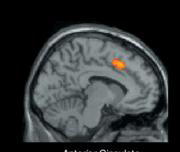

El profesor Matthew Lieberman y sus colaboradores añaden que esta respuesta común del cerebro al dolor físico y al que nos produce ser rechazados por nuestros semejantes tiene una explicación evolutiva, ya que sería importante para garantizar la supervivencia de la especie humana. Para efectuar este trabajo, cuyos resultados publicó ayer «Science», este equipo reclutó a trece universitarios que fueron sometidos a exploraciones con resonancia magnética por imágenes (MRI), tras participar en un juego de ordenador en el que dos figuras virtuales y el jugador humano se lanzan una bola. En un momento determinado, alegando a veces fallos técnicos, algunos estudiantes fueron apartados del juego. Al ser interpelados por los investigadores, esos jóvenes excluidos expresaron las mismas sensaciones de pesar y decepción que manifiestan las personas que sufren rechazo social. Las exploraciones que inmediatamente se practicaron a esas personas revelaron que se había activado el córtex anterior cingulado, una región del cerebro implicada en la respuesta al dolor físico.

En los voluntarios a los que se indujo ese mismo sentimiento de rechazo, pero que reaccionaron verbalmente con más escepticismo, se observó una activación en una parte del córtex prefrontal, que procesa nuestros sentimientos y regula el autocontrol. Susan Fiske, una especialista en psicología social de la Universidad de Princeton, ha destacado que las conclusiones de este estudio son muy «interesantes y provocadoras». Fiske recalcó que esta es la primera investigación que utiliza resonancia magnética por imágenes para analizar las bases biológicas de las interacciones sociales.